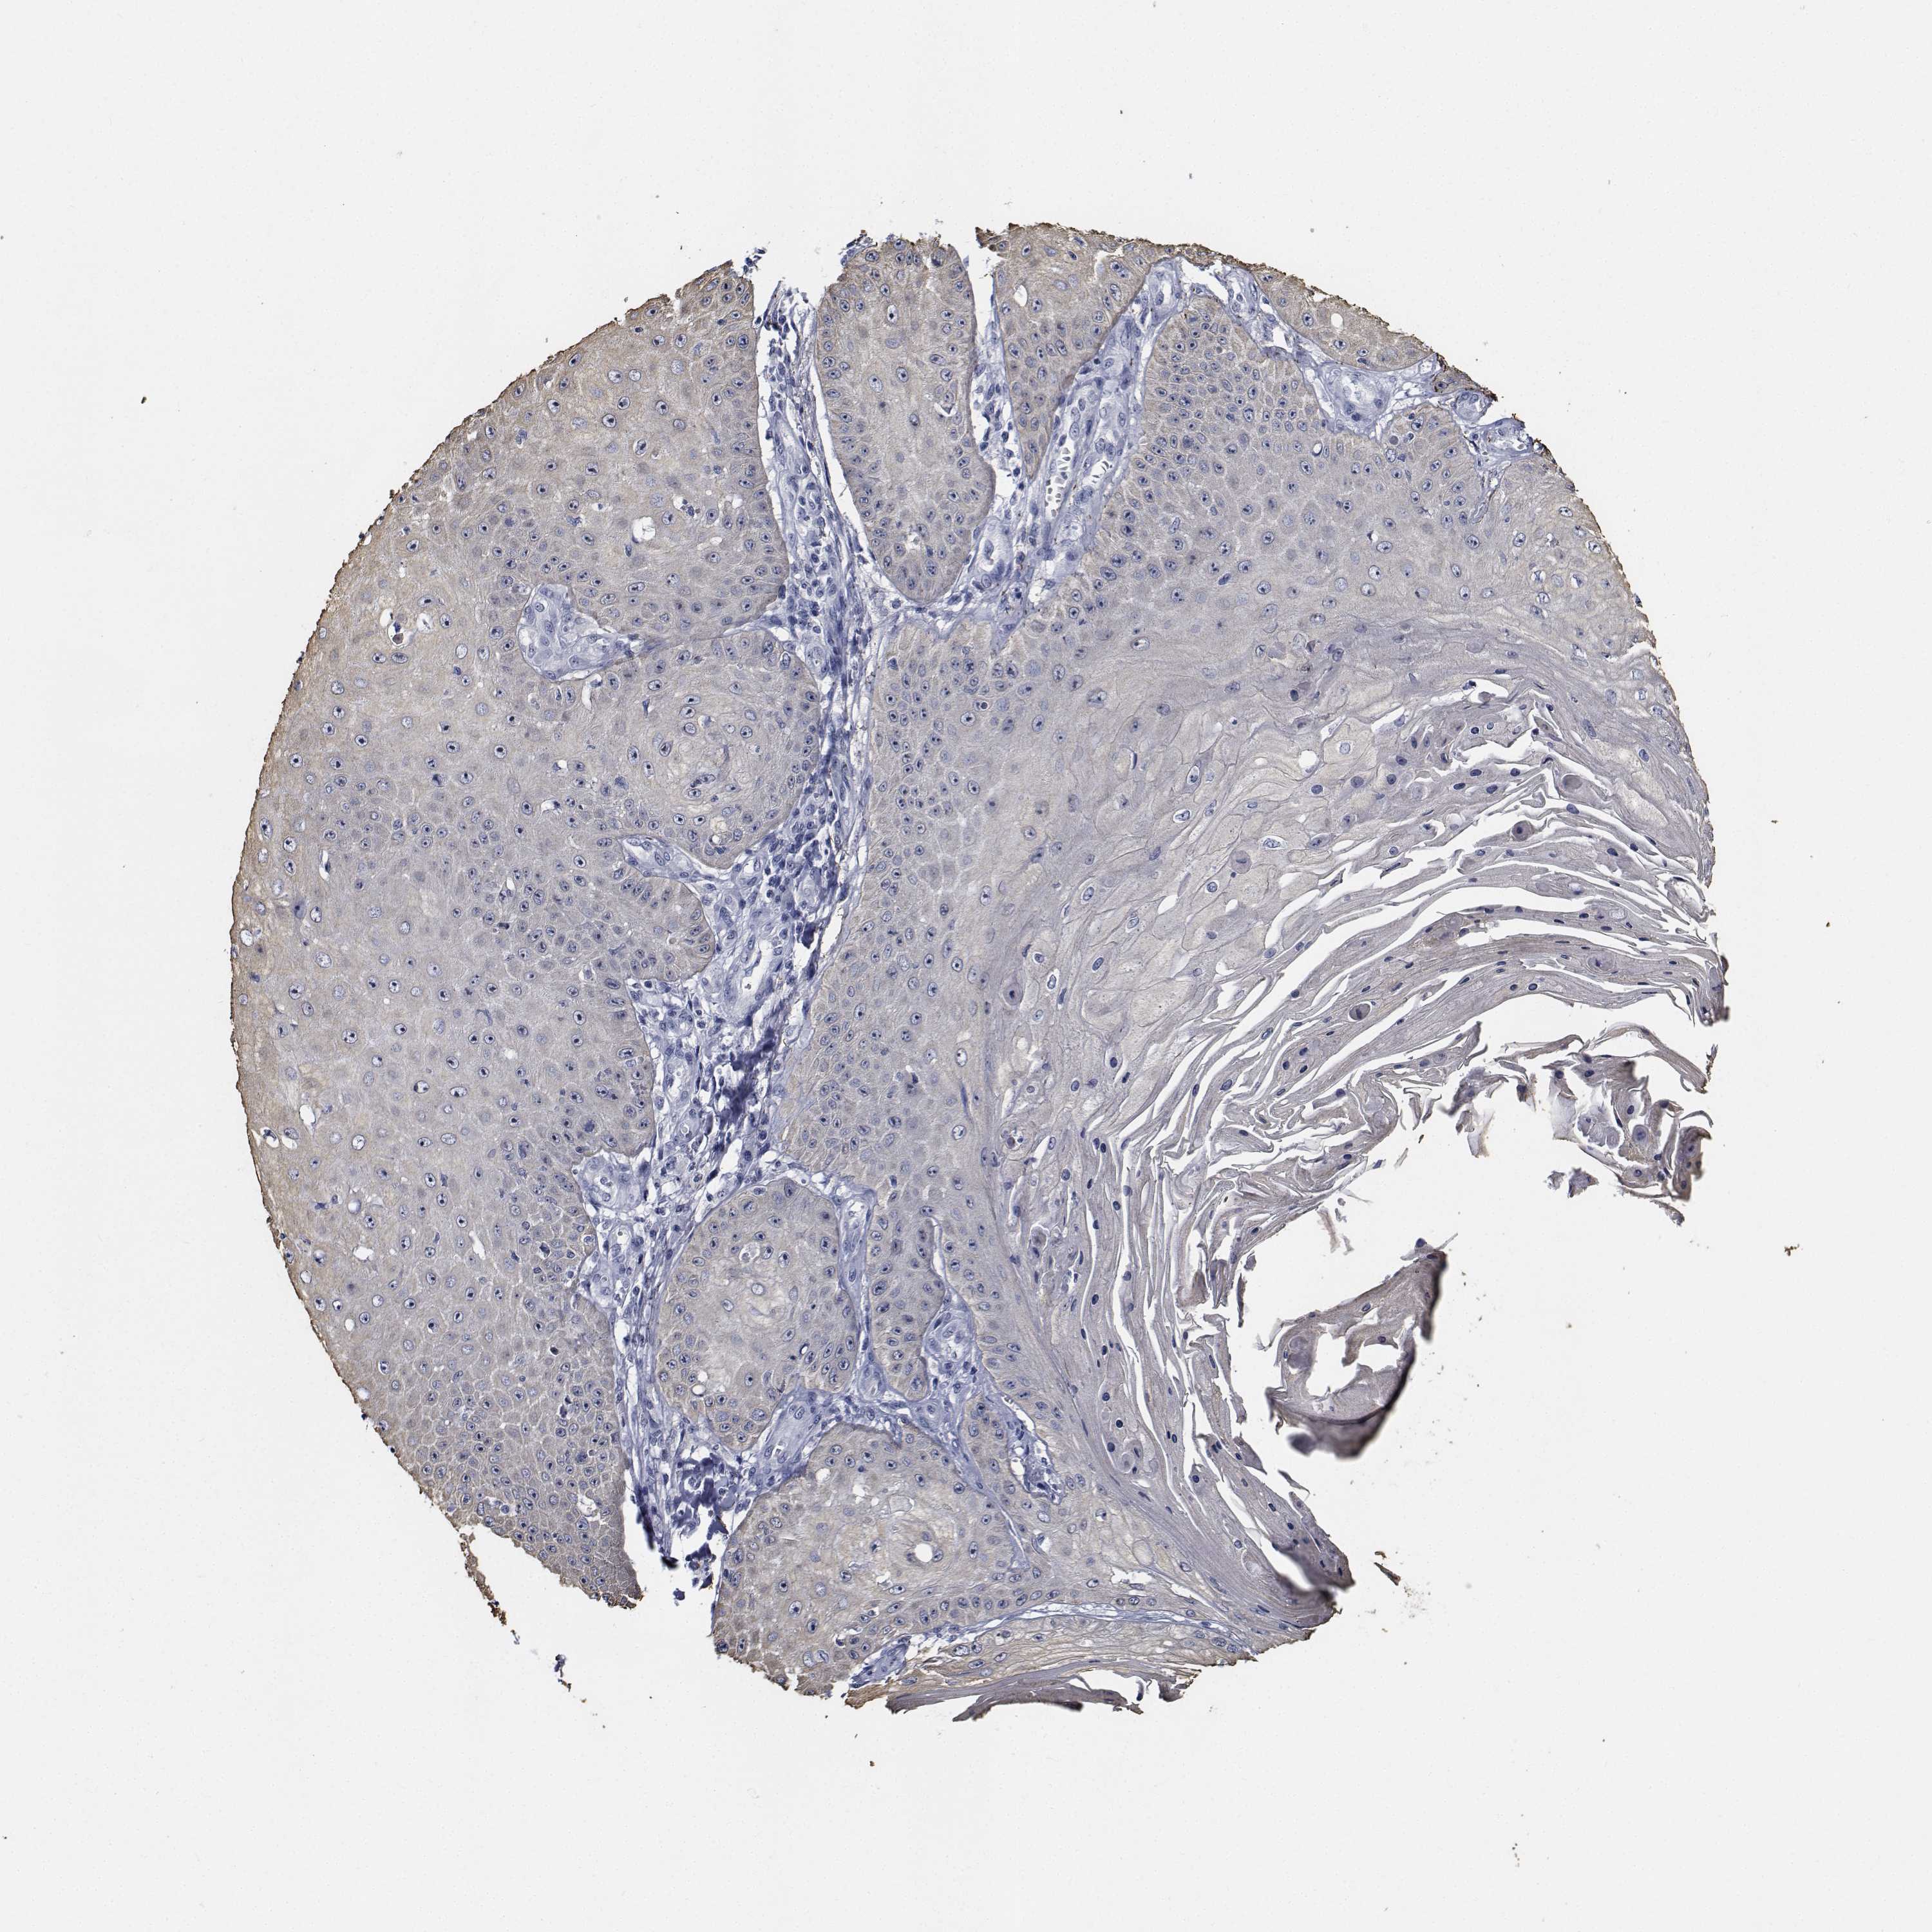

SKIN CANCER - Protein expressioni

A mouse-over function shows sample information and annotation data. Click on an image to view it in a full screen mode. Samples can be filtered based on level of antibody staining by selecting one or several of the following categories: high, medium, low and not detected. The assay and annotation is described here.

Each image is clickable and will lead to virtual microscopy that enables deeper exploration of all samples and also displays staining intensity scores, fraction scores and subcellular localization as well as patient and tissue information for each sample.

Antibody HPA028207

Antibody HPA028224

Antibody HPA028654

Staining

High

Medium

Low

Not detected

Intensity

Strong

Moderate

Weak

Negative

Quantity

>75%

75%-25%

<25%

None

Location

Nuclear

Cytoplasmic/membranous

Cytoplasmic/membranous,nuclear

Basal cell carcinoma

Squamous cell carcinoma, NOS